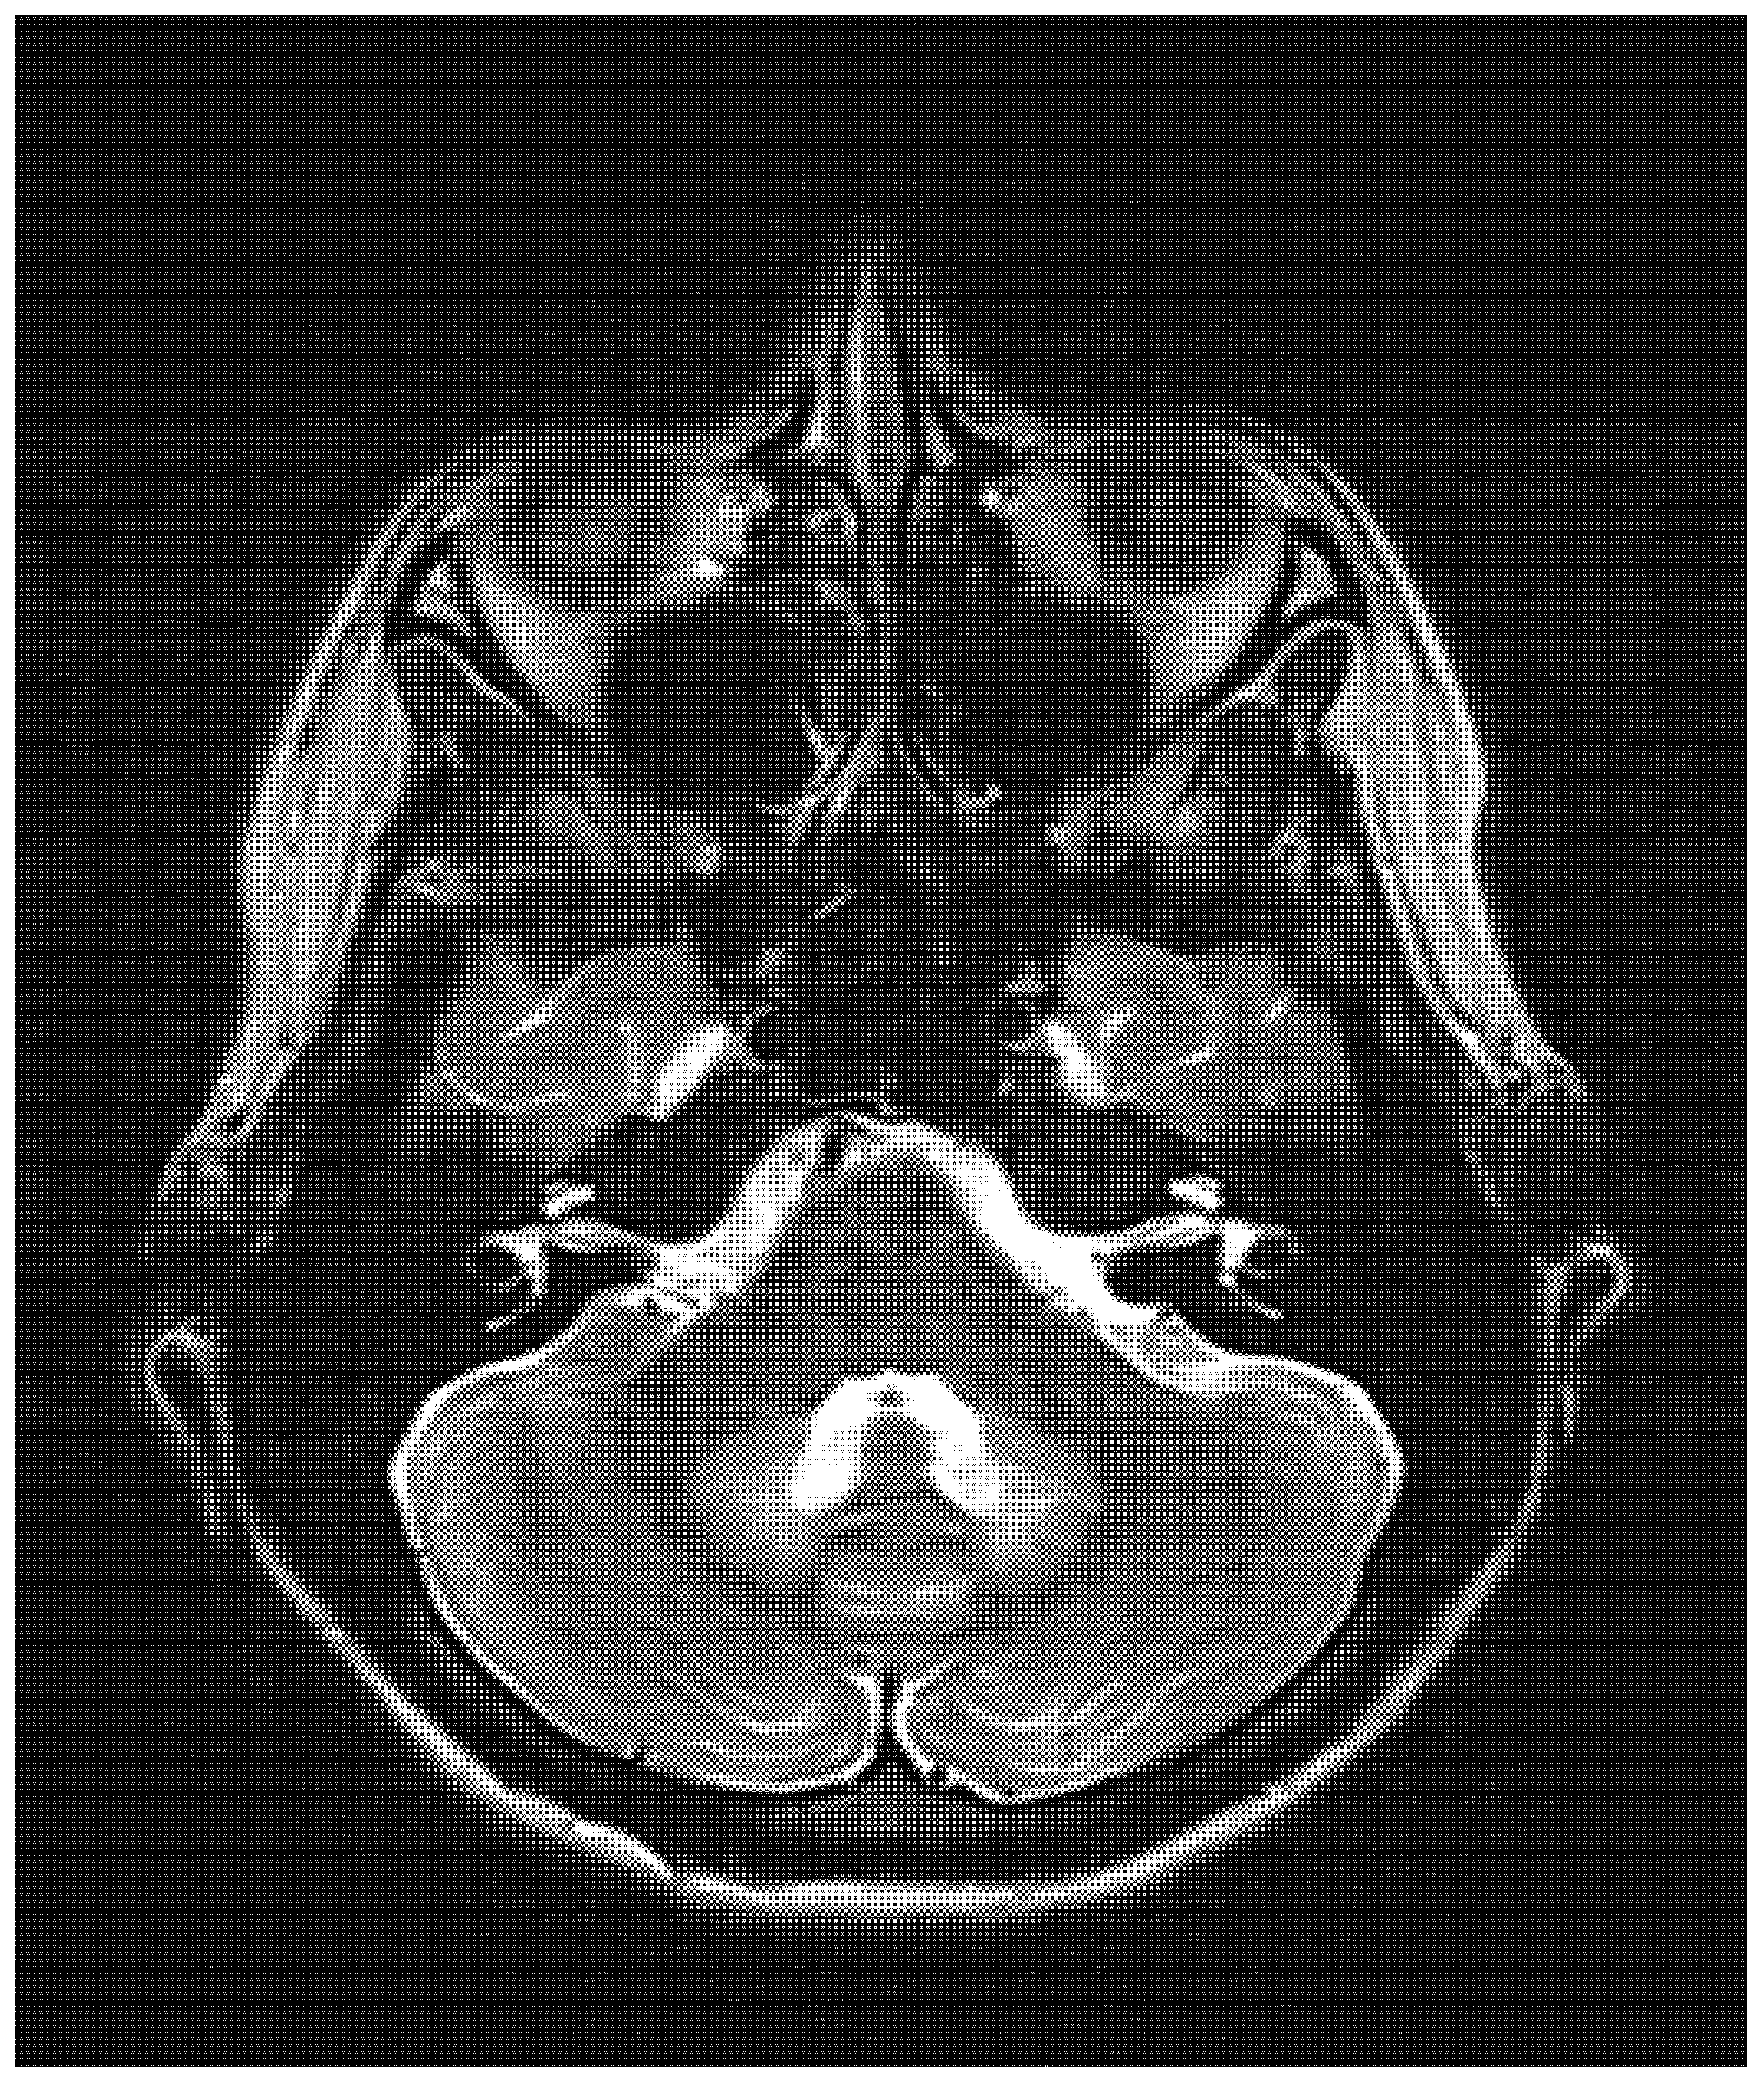

| Chang, 2021, USA [4] | 14, M | Clostridium difficile enterocolitis | N/A | N/A; N/A | Altered mental status; stiffening of 4 extremities; visual disturbance; slurred speech; gait instability | T2: symmetrical hyperintensity with corresponding diffusion restriction on DWI in posterior frontal, parietal, and occipital periventricular white matter and splenium of the corpus callosum | Near complete resolution | Near complete resolution |

| Chatzkel, 2010, USA [5] | 15, F | Crohn’s disease | N/A | 7; N/A | Ataxia; dysmetria | T2: Symmetrical hyperintensity in the dentate nuclei | Resolution | N/A |

| Omrani, Iran, 2020 [8] | 11, M | Febrile bloody diarrhea | 12 g | N/A; N/A | Tinnitus; hearing loss; aggressive behavior; generalized dystonia; generalized tonic-clonic seizure; decreased level of consciousness. | T2: Symmetrical hyperintensity in dentate nuclei, substantia nigra, globus pallidi, splenium of the corpus callosum, and centrum semiovale | Improvement | Partial improvement |

| Patel, USA, 2020 [9] | 8, M | Prophylaxis after small bowel transplantation | 1378.8 g | Three years; three years | Ataxia | T2: Symmetrical hyperintensity in the dentate nuclei, inferior olivary nuclei, putamen, and corpus callosum | Resolution | Resolution |

| Sudan, 2016, India [11] | 14, M | Acute abdominal pain | N/A | 3; 5 | Dysarthria; altered mental status; seizures. | T2: symmetrical hyperintensity in the optic tracts, dorsal midbrain, inferior olivary nuclei, peri-aqueductal white matter, superior and inferior colliculi, superior cerebellar peduncle, dentate nuclei, medulla oblongata, and cervical spinal cord segment extending from the cervicomedullary junction to C6-C7 level DWI: restricted diffusion in the splenium of the corpus callosum | N/A | Resolution |

| Sun, 2019, USA [12] | 11, M | Fusobacterium menigitis | N/A | 3 months; N/A | Vomiting; dizziness; vertigo; gait instability; bilateral lower extremity paresthesia | T2: Symmetrical hyperintensity in the dentate nuclei, dorsal pons, and medulla. DWI: no restricted diffusion | Resolution | Resolution |

| Yazdani, 2019, USA [13] | 17, M | Chronic diarrhea | N/A | N/A | Gait instability; abnormal unilateral lean | T2: Symmetrical signal hyperintensity in dorsal pons, dentate nuclei, dorsal medulla | Improvement | Resolution |